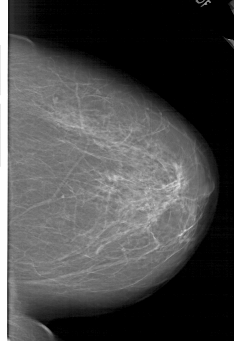

A_1952_1.RIGHT_CC

RIGHT_CC LINES 5791 PIXELS_PER_LINE 3976 BITS_PER_PIXEL 12 RESOLUTION 43.5 NON_OVERLAY